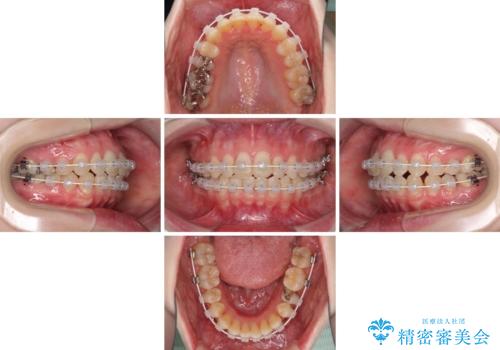

- 矯正装置

- 審美装置

治療途中で出産されたこともあり、当初予定よりも終了までに期間がかかってしまいました。

舌を前方に突出する癖があったため、上下前歯がなかなか接触しなかったことも治療期間が伸びた要因です。